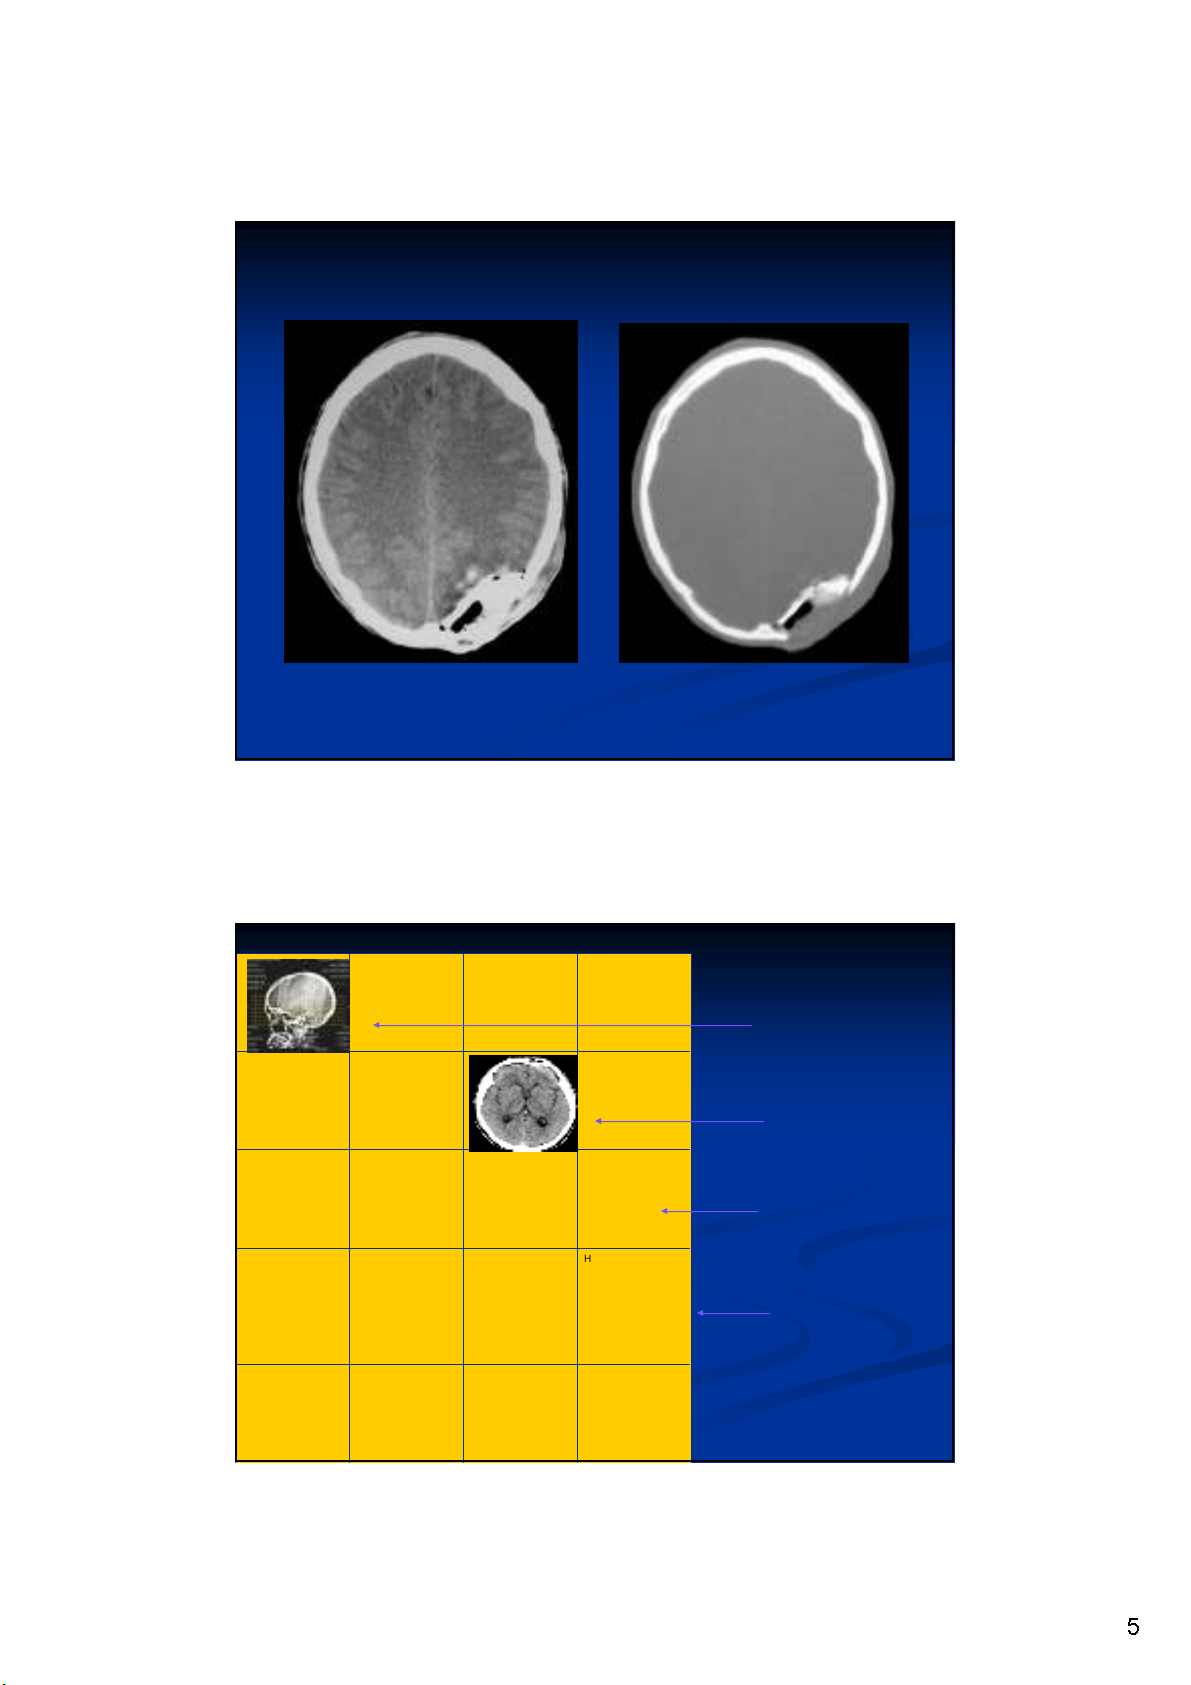

5

HH--tên Btên Bnh vinh vinn

NamNam--NN NgNgàày y

chchpp

SS!!IDID

ROIROI

kV, mAs kV, mAs

S#S#

W/LW/L

Hình nh v

Hình CT

Khung hình

PHIM CT

Các thông s